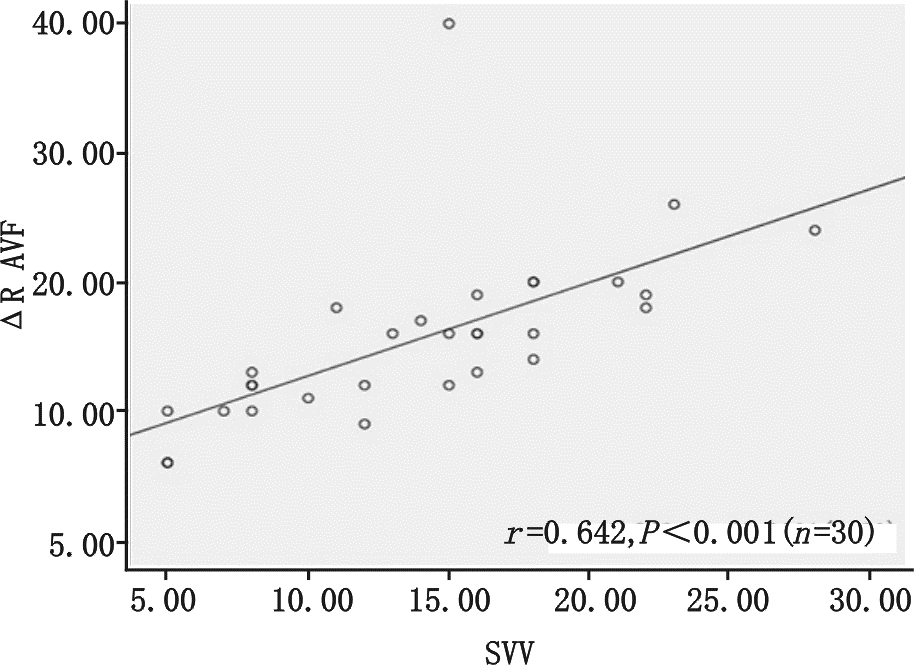

图 1显示ΔRⅡ随着呼吸周期显著的周期性变化,观察研究发现呼吸周期性ΔRⅡ与SVV呈正相关性(r=0.807,P<0.01见图 2),而呼吸周期性ΔR Ⅲ、ΔR AVF与SVV的相关性分别为(r= 0.453,P=0.016,r=0.642 ,P<0.01,分别见图 3、4);

| 图 4 呼吸周期性ΔR AVF与每搏量变异的相关性 |

机械通气患者,吸气相胸腔内正压增大,导致右心回流减少,同时右心后负荷增加,致右心每搏量减少,经过两三个心动周期后左心室的前负荷减少,就这样左心室的每搏量随着呼吸周期波动,在吸气末每搏量达最大值,呼气末每搏量为最小值,这种现象在心脏Staring 曲线的上升支更明显,在平坦支就不明显,所以这种变异是反应心脏前负荷的指标[4, 13]。心电图R波幅度随呼吸周期性变化的理论基础是“Brody 效应”[7],即心脏内血液的电阻比心肌组织低,心脏内血液越多电阻越小,传导至身体皮肤表面的电量越大。基于心肺交互原理,机械通气吸气相正压通气挤压肺血管床使左室前负荷增加,左室容积增加,故在吸气末左室前负荷最大即左室容量最大,此时R波波幅最大,每搏量也最大,而呼气末R波波幅最小,每搏量也最小。实际上R波波幅从原理上代表的是心室内的血容量,每搏量是代表着从心室射到主动脉的血容量,两者是同源的,所以心电图呼吸周期性R波波幅变化与每搏量变异相关,且能反应血管内容量。研究表明V5、V6的R波受左室在胸腔内位置影响较大,而Ⅱ、Ⅲ、AVF导联R波基本不受影响[14, 15],故本研究选择ΔRⅡ、ΔR Ⅲ、ΔR AVF为研究对象,结果显示ΔRⅡ、ΔR Ⅲ、ΔR AVF与SVV相关,而且我们发现ΔRⅡ与SVV相关性最好,明显优于ΔR Ⅲ、ΔR AVF,与先前研究结果一致[14],这可能与Ⅱ 导联与正常心脏电轴最接近的原因相关。大量研究表明SVV ≥12%为预测容量反应性的阈值[5],本研究比较SVV≥12%组与SVV < 12%组的HR、CVP 、MAP、CI,均显示差异无统计学意义,但全心舒张末期容积指数(GEDVI)两组间差异具有统计学意义,说明预测容量方面GEDVI优于HR、CVP 、MAP、CI,但其监测需行PICCO,费用昂贵,且操作不便。笔者通过受试者工作特征(ROC)曲线评估ΔRⅡ预测SVV≥12%能力,其曲线下面积(AUC)为0.910±0.055(P<0.01),与PPV预测SVV差异无统计学意义。以ΔRⅡ临界值为11.5%预测SVV≥12%,其敏感度80%,特异度90%,说明在感染性休克机械通气的患者ΔRⅡ能准确反应或预测SVV值,虽然本实验未行容量负荷试验,但这给我们启示是否ΔRⅡ可作为SVV替代指标应用于机械通气患者辅助评估容量反应性,待进一步研究证明,进而开发应用ΔRⅡ这个新指标在心电监护仪上持续监测,如同PPV一样。